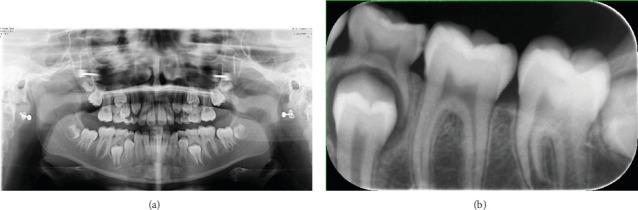

绒毛瘤是一种具有正常组织学的组织块,类似于身体的一部分,但与它所在的部分不同。它不同于错构瘤组的病理是正常组织,但杂乱无章,发现在一个异常的位置。在口腔发生骨性脉络瘤病变的文献很少,大多数病例已报道在舌头。很少发生在牙间龈。事实上,虽然有许多老年人的病例报道,但脉络膜瘤被认为是一种发育异常,涉及年轻人。鉴别诊断包括软骨化生、多形性腺瘤、唾液腺组织,以及可能导致口腔错构瘤的炎症或创伤性病变。在这个病例报告中,我们提出了一个病例骨性脉络瘤起源于下颌,后颊龈在一个年轻的女性患者。

Choristoma is a mass of tissue with normal histology similar to a part of the body that is different from the one in which it is located. It differs from the hamartomatous group of pathology which is normal tissue, but disorganized, found in an abnormal location. Documentation of the occurrence of osseous choristoma lesions in the oral cavity has been scarce, and most of the cases have been reported in the tongue. It is very seldom to arise from the interdental gingiva. Indeed, choristoma is considered a developmental anomaly, involving younger individuals, although many cases among older adults have been reported. The differential diagnoses include cartilaginous metaplasia, pleomorphic adenoma, salivary gland tissue, and the lesions of inflammatory or traumatic origin that may give rise to hamartomas in the oral cavity. In this case report, we present a case of osseous choristoma arising from the mandibular, posterior buccal gingiva in a young female patient.